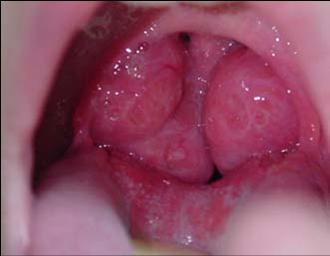

டான்சில் என்பது தொண்டையில் இரு பக்கங்களிலும் உள்ள இரு உருண்டையான திசு தொகுப்பு ஆகும் . இதை நோய்க்கிருமி தாக்குவதால் வரும் வீக்கமே டான்சிலைட்டிஸ் – Tonsillitis எனப்படுகிறது .